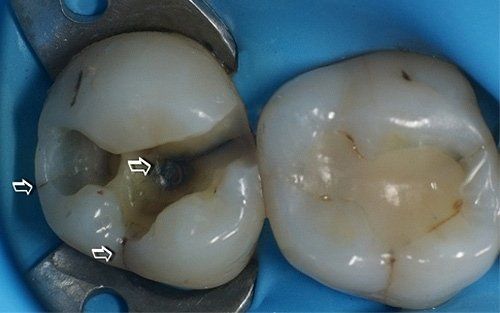

Upon removal of the old restoration, the diagnosis will be confirmed by visualising fracture lines that may involve various areas of the tooth (usually the base of one or more cusps, extending to the entire roof of the pulp chamber and root extension). Not all cracks are equally severe: we believe that preserving the vitality of the pulp, where possible, along with protecting the affected cusps from cracking, is the most conservative and long-term effective therapy for tooth health. In the "Direct restorative dentistry" section and especially in the "Indirect restorative dentistry" section, you will find a series of restorative solutions for the cracked tooth.